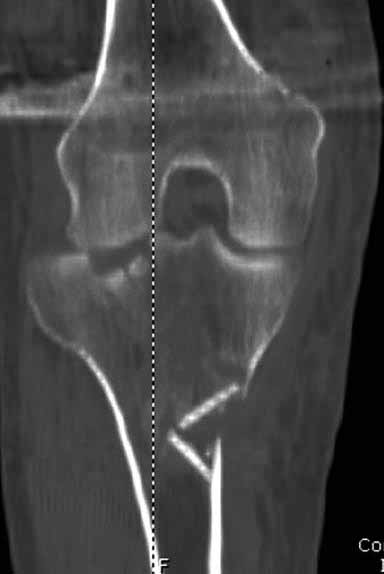

На снимке типичный перелом медиального тибиал плато с передним смещением (подвывих) по Schatzker IV. Консервативное лечение без медиальной опоры не может удержать деформирующие силы, и из-за вторичного смещения мыщелка конечность смещается в варус. Кроме передних смещений еще встречаются сложные фронтальные варианты переломов, и тогда голень подвывихивается кпереди.

А в данном случае мыщелок сросся со смещением кпереди и ротирован. За счет интактной наружной колонны опороспособность конечности сохранена, но остается варус и экстензия конечности. Для предоперационного расчета необходимо сделать на всю длину конечности рентгенограмму, а в остром периоде КТ и 3-мерный снимок помогут лучше ориентироваться в характере перелома.